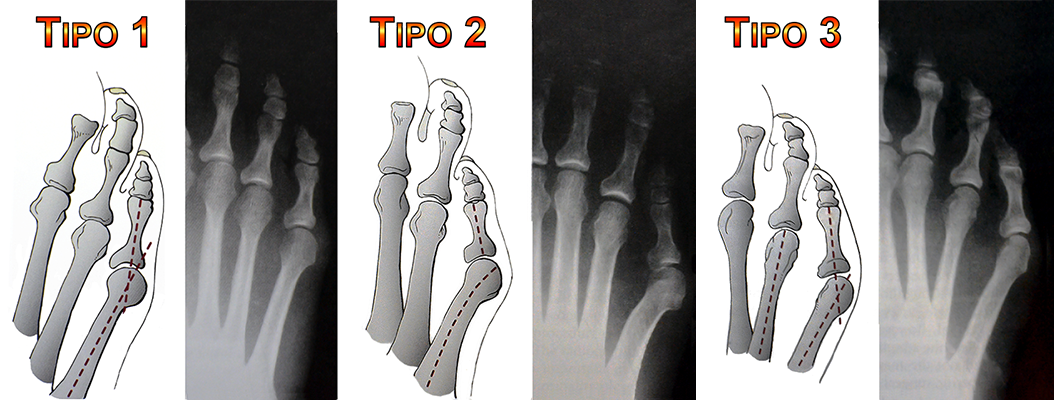

Algumas alterações anatômicas do pé também estão relacionadas à progressão da deformidade e são classificadas em três tipos:

Tipo 1: Alargamento e protusão da cabeça do 5º metatarso

Tipo 2: Curvatura lateral anormal do 5º metatarso

Tipo 3: Aumento do ângulo entre o 4º e 5º metatarsos

A avaliação radiológica do pé é importante para definir o grau e o tipo de deformidade presente.